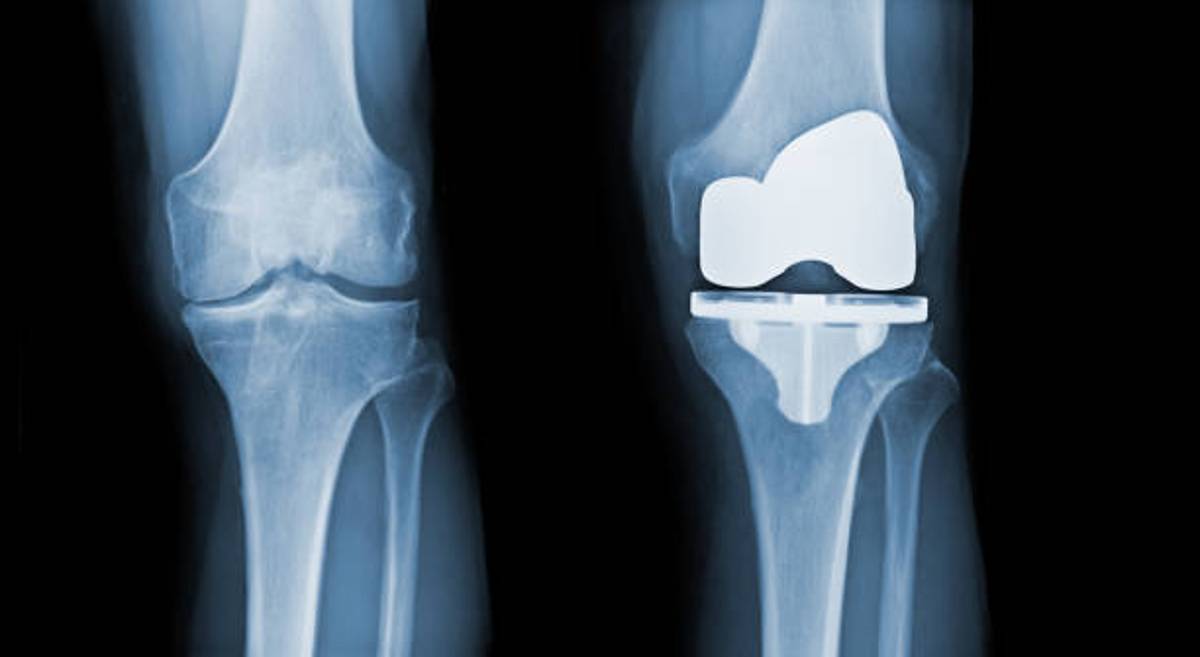

total-knee-replacement-surgery

69 years old got back on her f...

Prosthetic joint infection (PJI) remains a devastating complication after total knee arthr...

Dr. J V Srinivas 19 December 2022